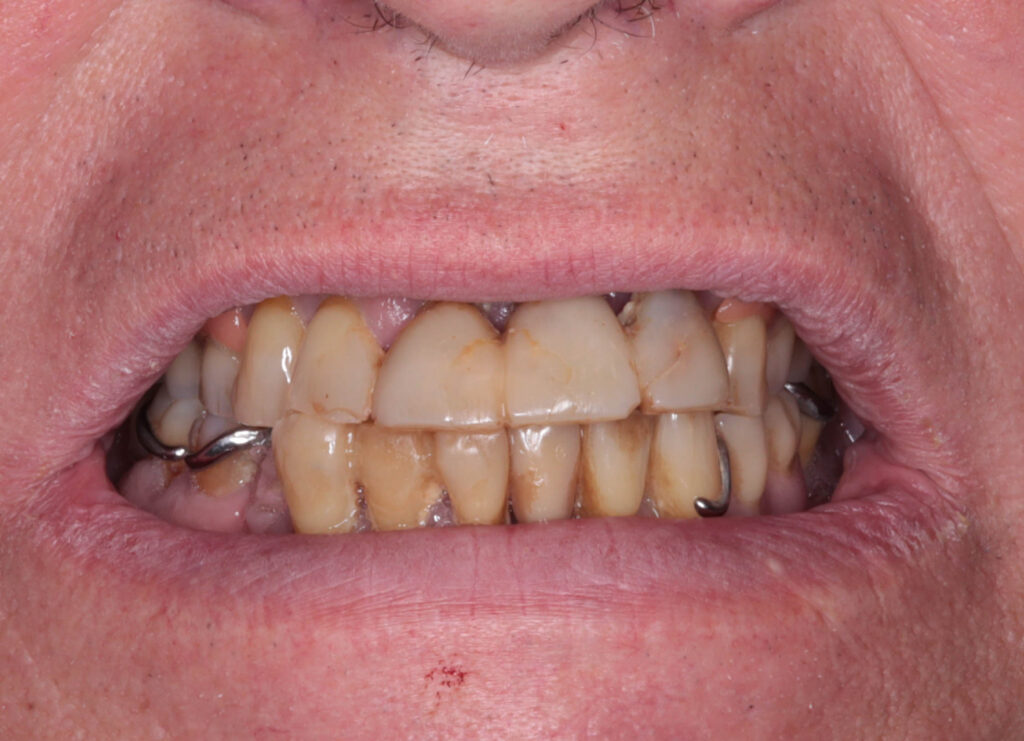

Ситуация до лечения

пациент до имплантации